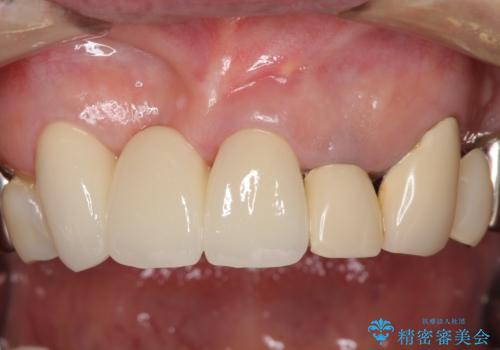

仮歯に置き換えた時点で見た目が大きく改善され、人目を気にすることがなくなりました。

オールセラミッククラウンは、仮歯以上に快適な舌触りや、本物の歯のような外観となり、患者様には大変満足していただけました。